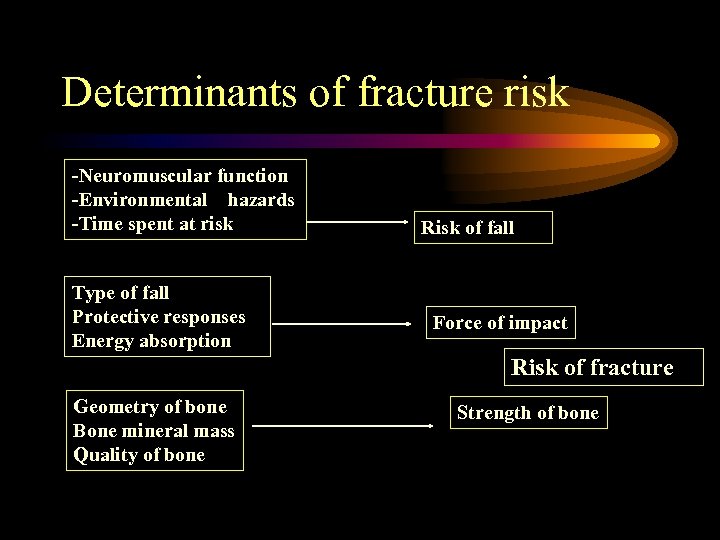

Determinants of fracture risk -Neuromuscular function -Environmental hazards -Time spent at risk Type of fall Protective responses Energy absorption Risk of fall Force of impact Risk of fracture Geometry of bone Bone mineral mass Quality of bone Strength of bone

Determinants of fracture risk -Neuromuscular function -Environmental hazards -Time spent at risk Type of fall Protective responses Energy absorption Risk of fall Force of impact Risk of fracture Geometry of bone Bone mineral mass Quality of bone Strength of bone